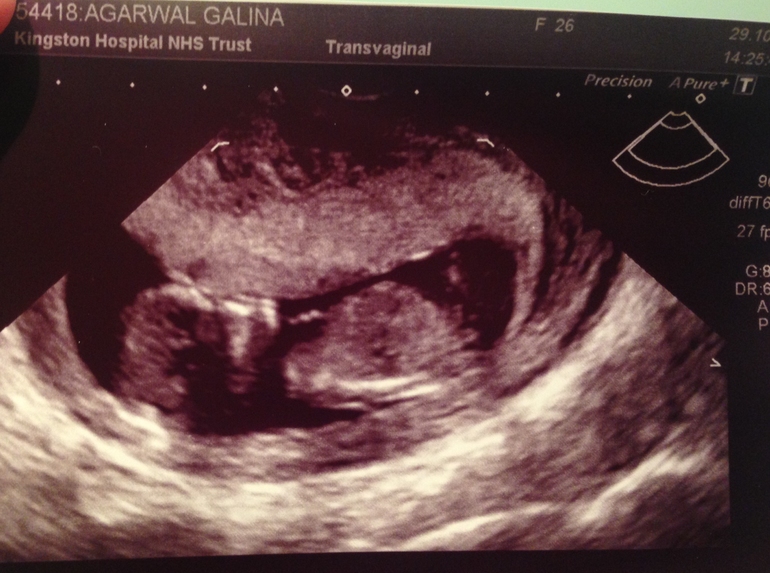

Показали! Лежал наш малыш спиной, руки в боки, обиделся на тётю-врача, которая сказала, что его не видит, а он тут вот какой целых 52 миллиметра!

Всё у нас правильно и хорошо! Писать эти данные не буду: у всех всё одинаковое)) срок 11 недель 5 дней! Значит, я точно угадала и знала день, когда малыш решил к нам снизойти 22 августа, а УЗИ только это подтвердило)) потом началось самое интересное!

И вот фоточка нашего нехочуки! Видимо, характер явно не в покладистого папу)) хе-хе))